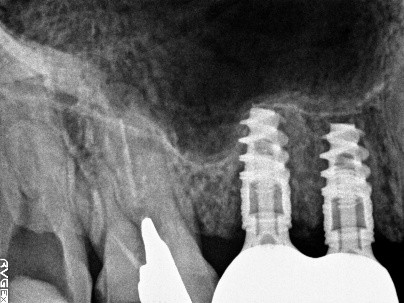

レントゲンで詳しく診てみると、虫歯が歯根のほうまで進行し、保存することができないことがわかり、抜歯しました。抜歯後、骨が大きく欠損していましたので、骨造成を行いインプラントを2本埋入しました。

所感

抜歯後の欠損したところを補う方法には、部分入れ歯、ブリッジ、インプラントがあることを説明したところ、自分の歯と同じような感覚で嚙むことができるインプラントを選択されました。この方は、2016年に右下にインプラント治療をし、インプラントの良さを十分に理解しておられましたので、今回も2本歯を失ったところにインプラント治療を希望されました。今回もX-Guideを使った埋入で、安心安全に行うことできました。